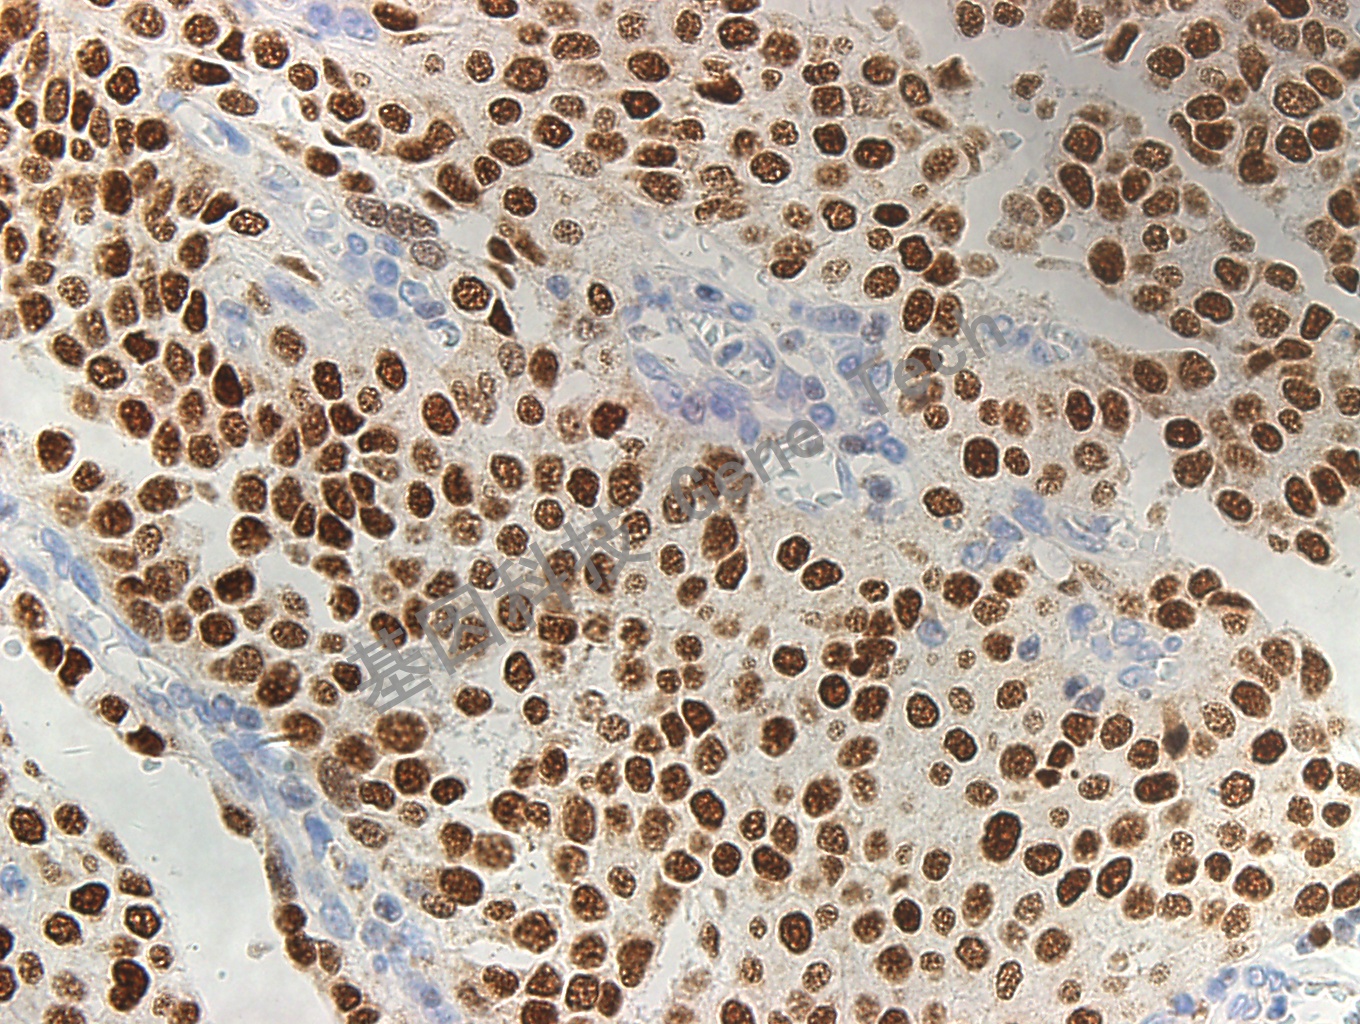

膀胱浸润性尿路上皮癌石蜡切片,用 GATA3(GT2187)染色,细胞核阳性,DAB 显色。